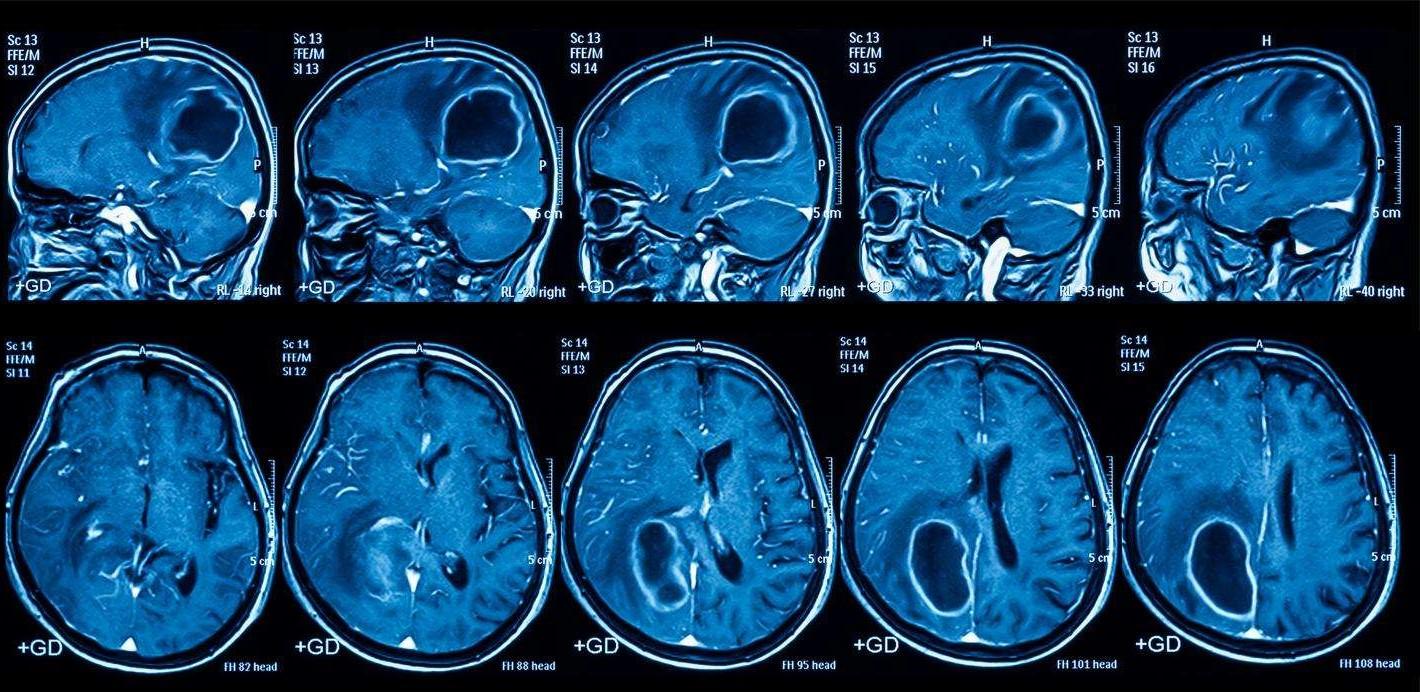

The image on the bottom left shows how the brain of a person who had Huntington's was atrophied (smaller) compared to the non-Huntington's brain. This is evidenceofneuralloss.